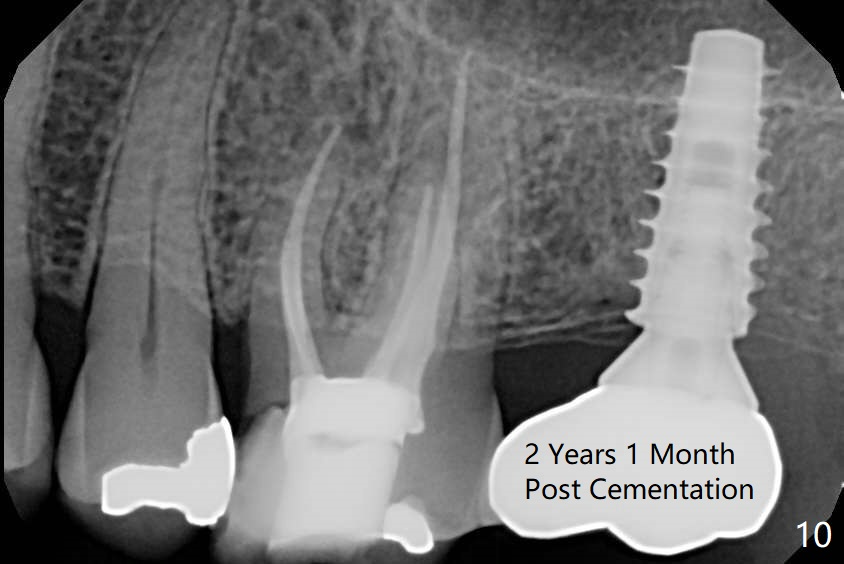

The ridge is pointed at the site of #15 (Fig.1). A 1.2 mm initial drill is used to start osteotomy for 10 mm, followed by an incision over the ridge mesiodistally for ~ 8 mm. After tapping the #15 C blade, the 1st Bone Expander 1.0/1.6 mm) is inserted for ~ 11 mm (Fig.2, 20 Ncm). Bone expansion continues until #4 Expander (2.4/3.7 mm, Fig.3). When 4x11 mm and 4.5x11 mm dummy implants are placed (Fig.4), insertion torque remains 20 Ncm. Following placing allograft with 3-4 amalgam carriers, a 5x11 mm IBS implant is placed with 20 Ncm (Fig.5,6). In fact the implant turns when an abutment is placed. When the implant is re-inserted, torque decreases to 10 Ncm. Instead a healing screw is placed. The low torque value is due to soft bone and failure to underprep. #4 Expander (Fig.3) seems larger than 4.5 mm implant (Fig.4). #3 Expander (1.7/3.1 mm) should have been used prior to definitive implant placement. The implant appears to have osteointegrated 3 months postop (Fig.7); impression is taken. The bone density at the crest increases 1.5 years post cementation (Fig.8 *, as compared to Fig.6), although there is mild bone loss. Implant placement should be deep when bone expansion is carried out. The tooth #14 develops a buccal fistula, corresponding to periapical radiolucency of the mesiobuccal root (Fig.9 white >). The abutment of #15 may be incompletely seated (black <). PA taken when RCT of #14 is finished does not show the incomplete seating of the abutment (Fig.10). Since there appears no history of abutment screw loosening, the abutment is not reseated when #14 is prepared for crown. Recall 3 years 7 months post cementation shows incomplete seating of the abutment (Fig.11 >). After crown proximal reduction (Fig.12 *) and clockwise turn of the crown, the abutment appears to be completely seated. When the case returns from lab, the separate crown and abutment cannot be connected to the fixture because of soft tissue adaptation and change in a month. The abutment is reseated to the fixture analog in the model and the crown is recemented with temp bond (in case of misalignment) while making sure that the crown has the best proximal contact with the neighboring crown. With the abutment and crown in a unit, it is much easier to reseat the abutment with normal proximal contact. The torque is 20 Ncm. The access hole is closed with Cavit.